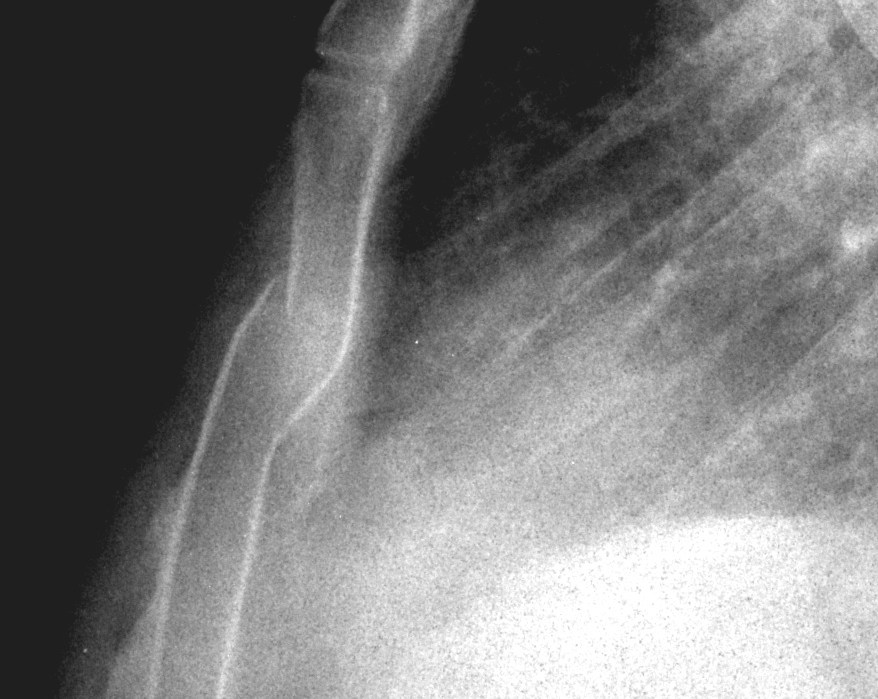

From www.cmaj.ca

Stairlike fracture of the sternum CMAJ Pain In Sternum And Back Pain It could also be due to a. Sternum pain can result from problems with muscles and bones near the sternum, as well as the sternum itself. Learn about the possible causes of chest and back pain, such as heart disease, lung problems, muscle strain, and more. A heart attack happens when the flow of blood to your heart tissue becomes. Pain In Sternum And Back Pain.

From contempo3.blogspot.com

Sternal Fracture Sternum Pain After Car Accident Pain In Sternum And Back Pain Find out how to describe your pain and when to seek. Chest pain and back pain occurring together may indicate a serious condition involving your heart, lungs or biliary system. A heart attack happens when the flow of blood to your heart tissue becomes blocked. Chest and back pain may occur together for many reasons, ranging from a bruised rib. Pain In Sternum And Back Pain.